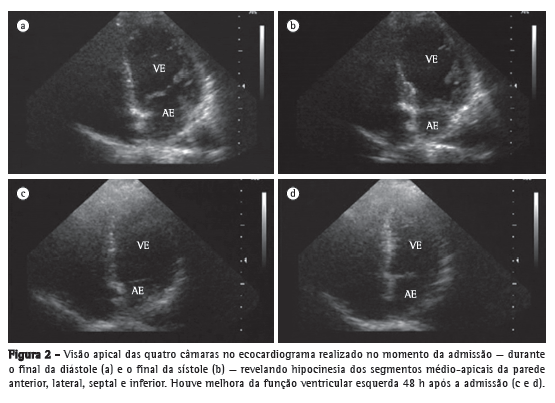

O ecocardiograma transtorácico com janela ecocardiográfica limitada revelou hipocinesia dos segmentos médio-apicais da parede anterior, lateral, septal e inferior (Figuras 2A e 2B), fração de ejeção de 25% e disfunção diastólica com relaxamento alterado. O formato do ventrículo esquerdo (VE) era semelhante ao de um pote de pesca japonês, de base arredondada e pescoço estreito, utilizado para a captura de polvos, chamado de takotsubo, do qual o termo "cardiomiopatia de takotsubo" é derivado.

Seis horas após a admissão, a paciente apresentou choque cardiogênico. Recebeu altas doses de catecolaminas (dobutamina e noradrenalina), foi submetida a intubação endotraqueal e necessitou de ventilação mecânica. Foi submetida a cateterismo cardíaco de emergência, o qual revelou que suas artérias coronárias estavam normais. O choque cardiogênico foi revertido em 48 h, com uma fração de ejeção do VE de 60% (Figuras 2C e 2D). Após 2 anos de seguimento, a paciente apresentava função ventricular esquerda normal e QTc de 388 ms (Figura 1), sem grandes eventos cardíacos adversos.